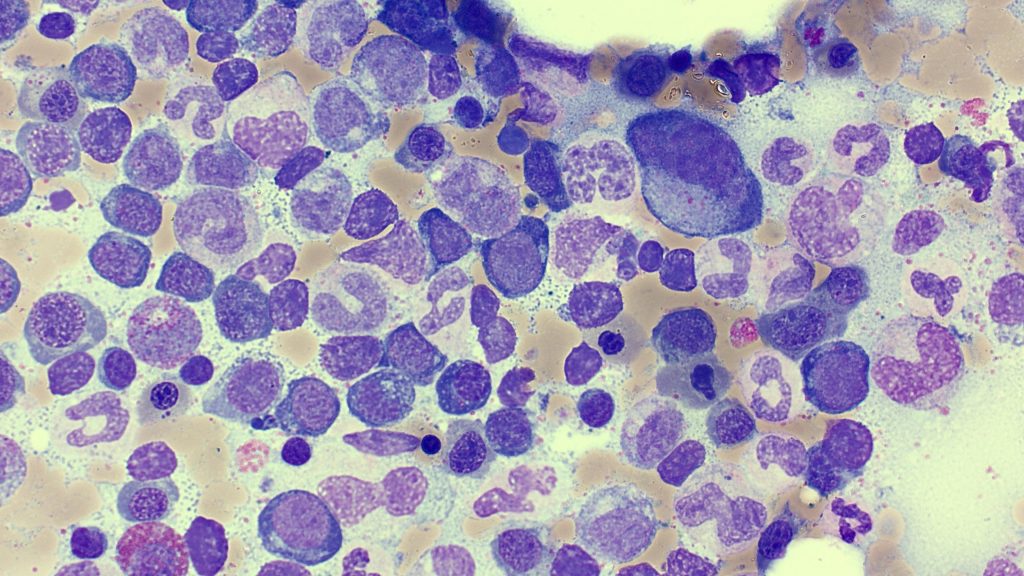

Multiple Myeloma

Dohle bodies

Intranucleolar inclusions

Multiple nuclei

Myeloma Cells

More…